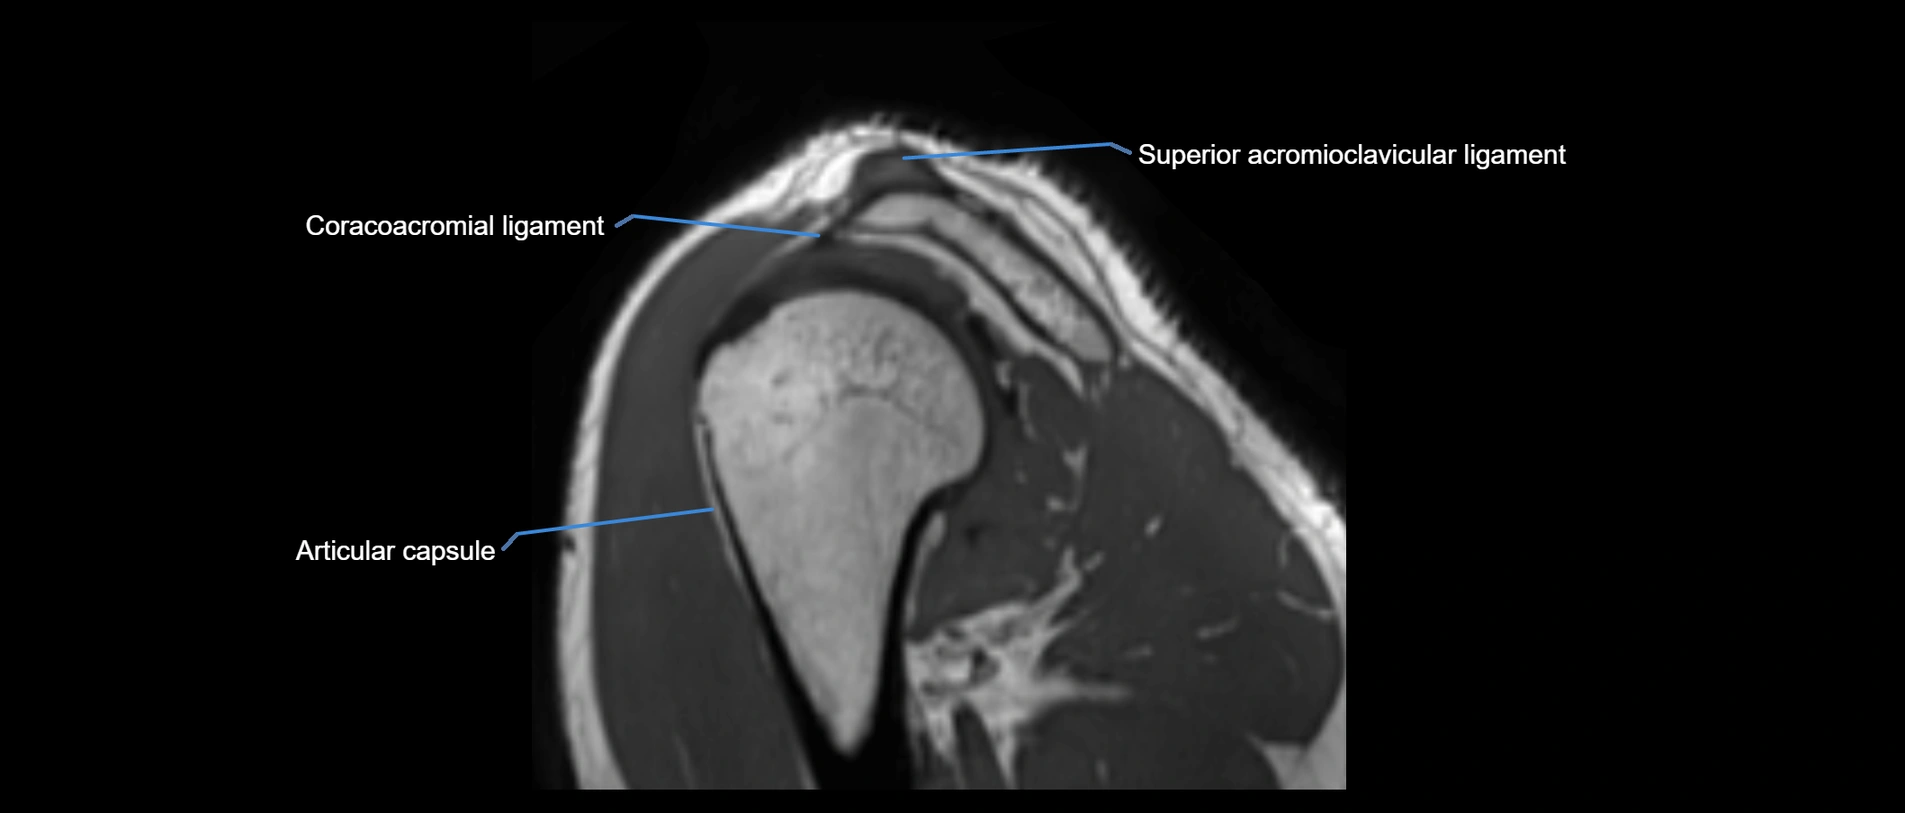

MRI images

image